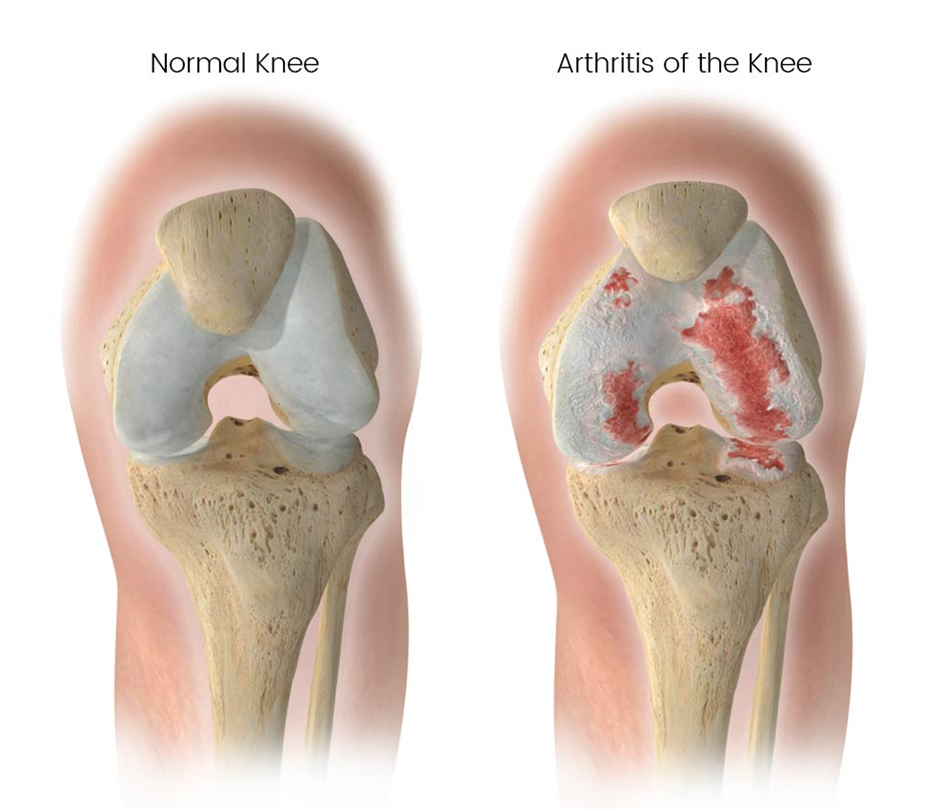

Knee osteoarthritis (OA) is a common joint problem that occurs when the cartilage in the knee wears down over time. This leads to pain, stiffness, and difficulty in movement. It mostly affects people above the age of 50 but can also develop earlier due to injuries or other risk factors.